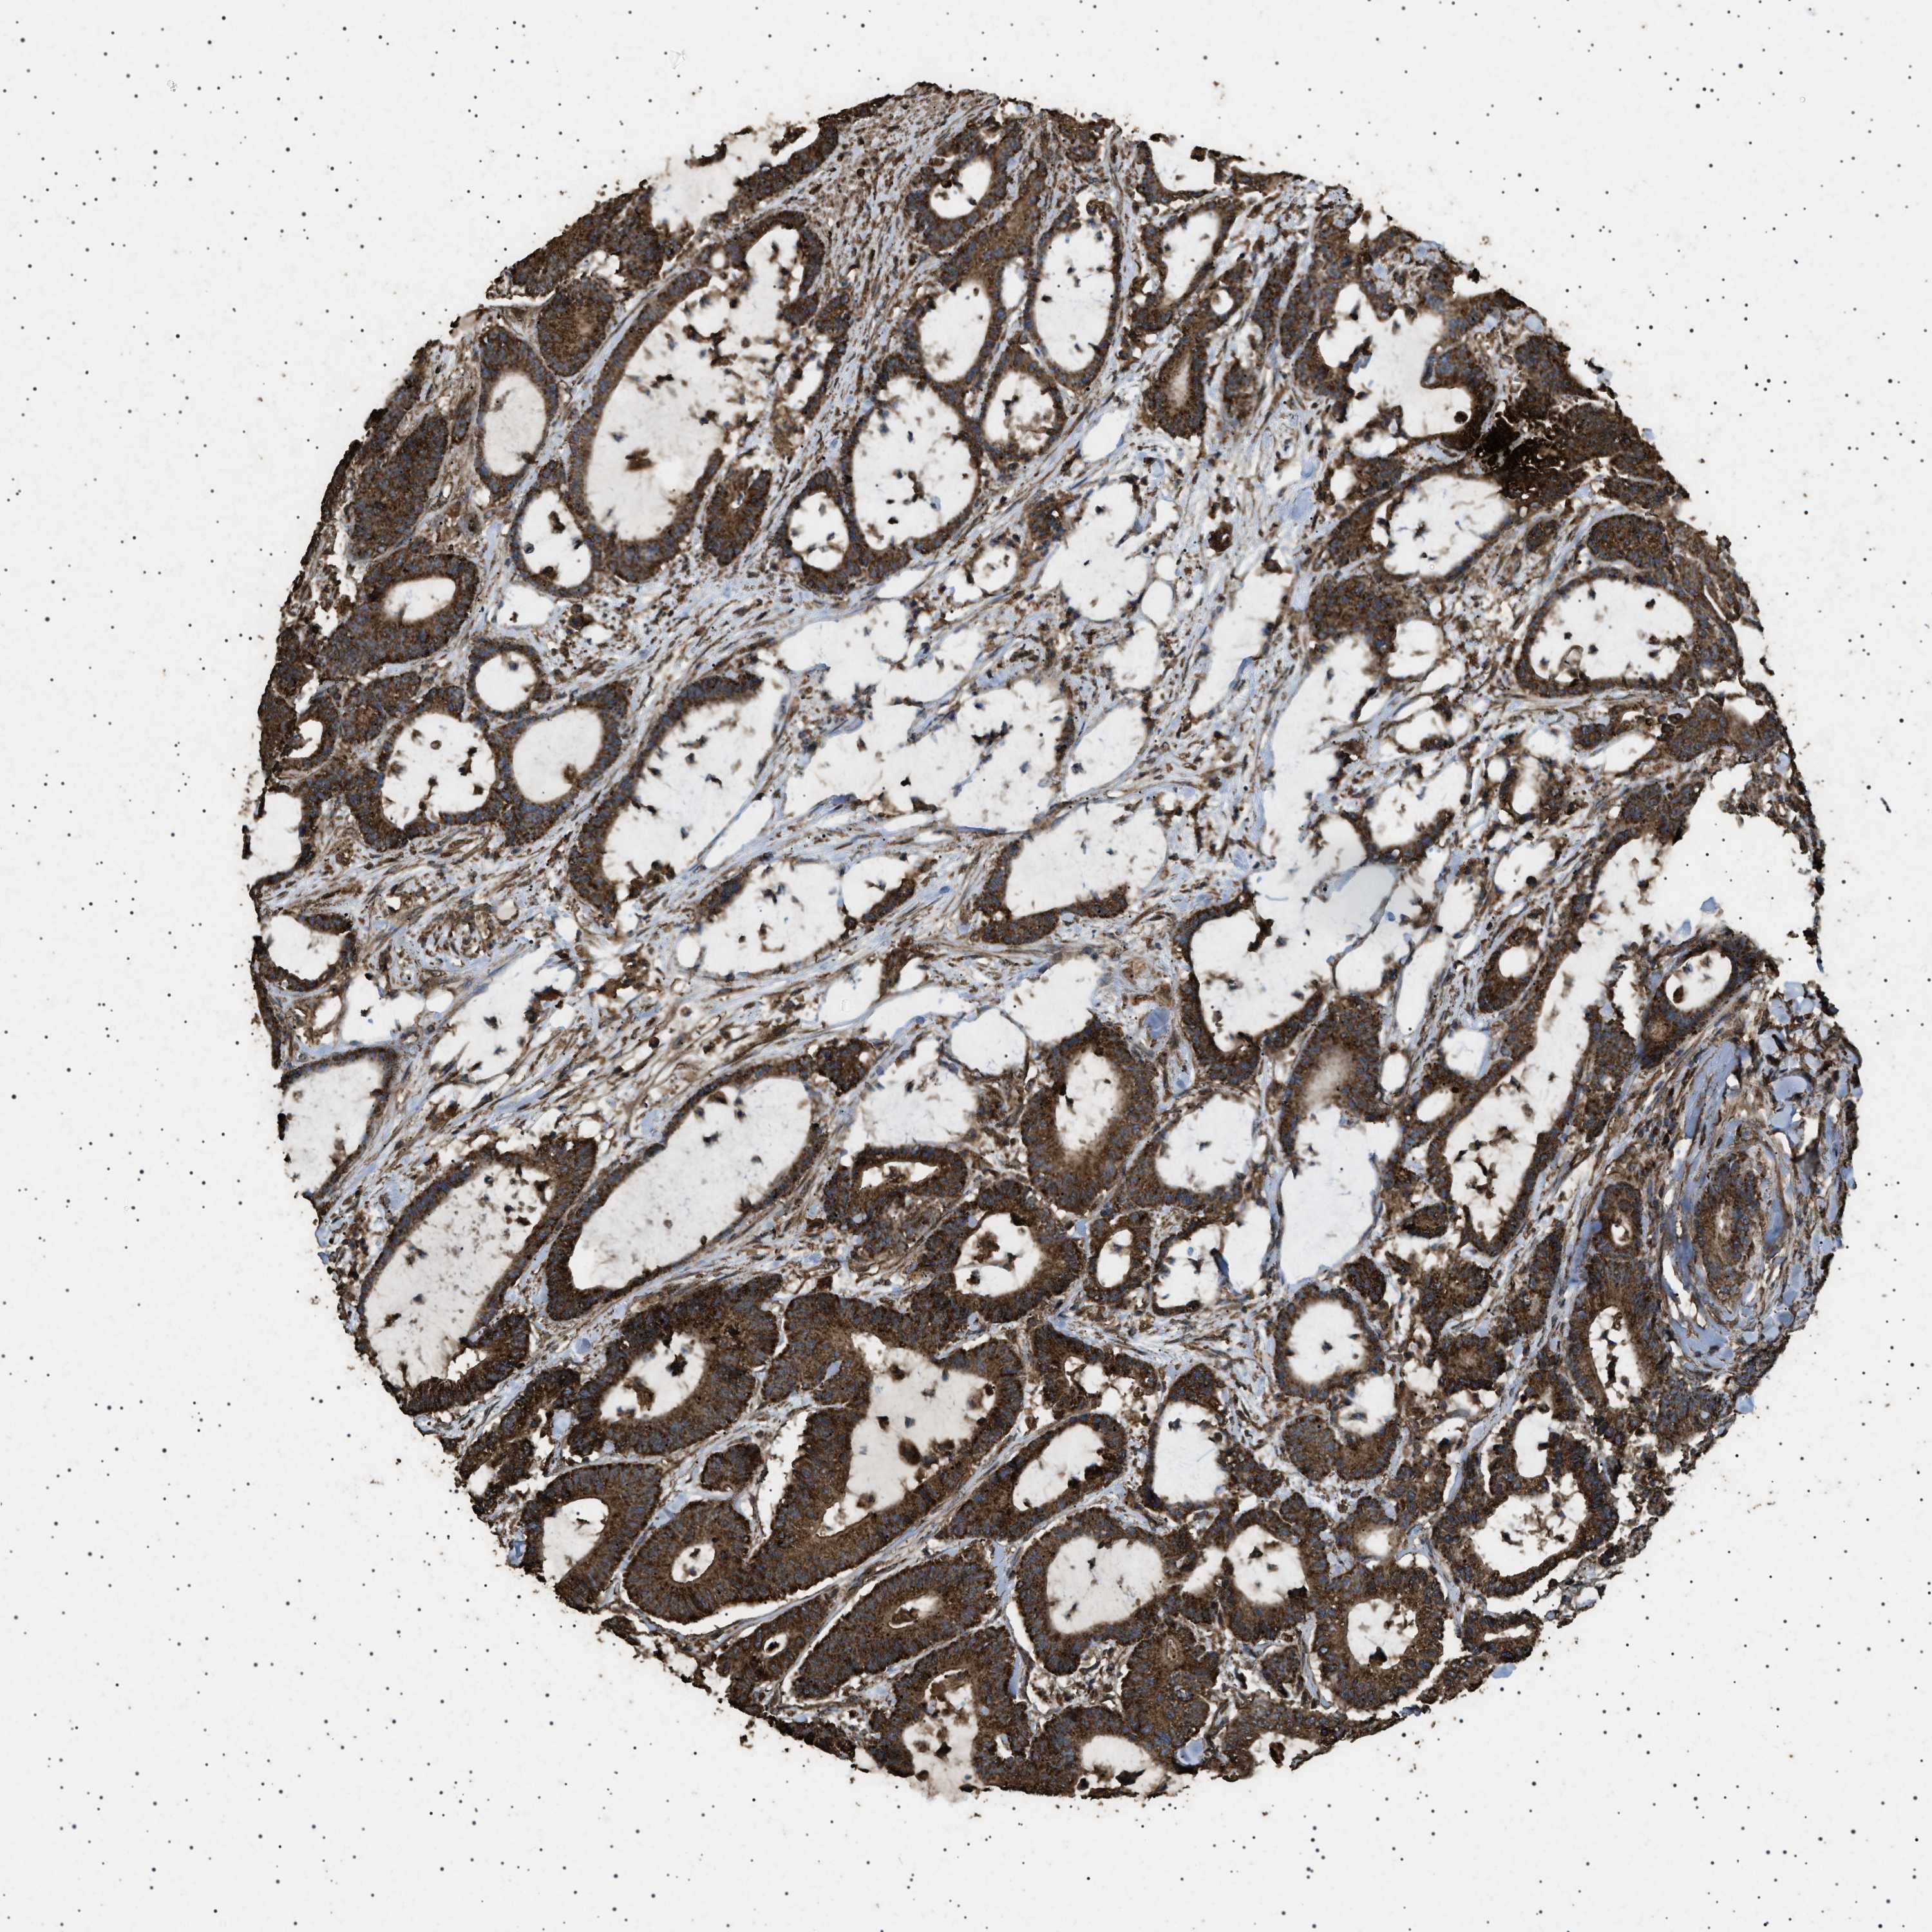

CANCER COLORECTAL CANCER Show tissue menu

Colorectal cancer

Human cancer

Colon adenocarcinoma